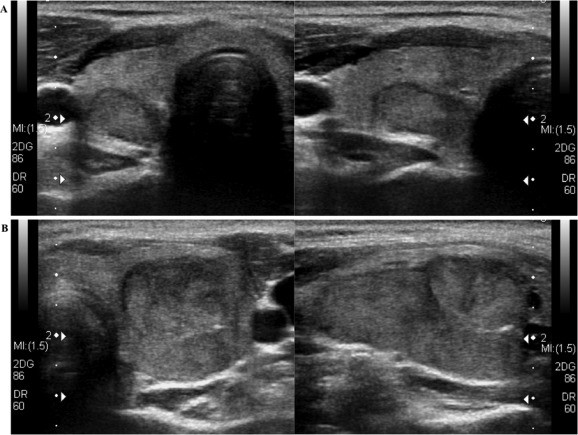

Thứ hai: Do việc áp dụng rộng rãi các phương pháp chẩn đoán như siêu âm, chọc hút tế bào kim nhỏ ở các cơ sở y tế trong và ngoài công lập.

Việc chẩn đoán ung thư tuyến giáp típ nang không thể phát hiện thông qua xét nghiệm chọc hút tế bào kim nhỏ (FNA) thông thường mà chỉ được phát hiện khi phẫu thuật bóc khối u xét nghiệm mô bệnh học.

Với việc xét nghiệm chọc hút bằng kim nhỏ chỉ hướng đến U tân sản thể nang (Được xếp vào nhóm IV của hệ thộng Bethesda ) các bác sỹ lâm sàng cần kết hợp thêm kết quả của các xét nghiệm như T3, FT4, TSH, Anti TPO, Antin TG…, kết quả chuẩn đoán hình ảnh như siêu âm, chụp xạ hình… để quyết định hướng điều trị cho bệnh nhân .